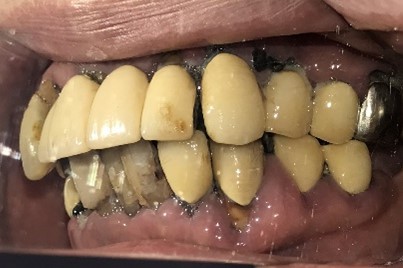

After

【義歯を装着したところ】

【義歯を外したところ】